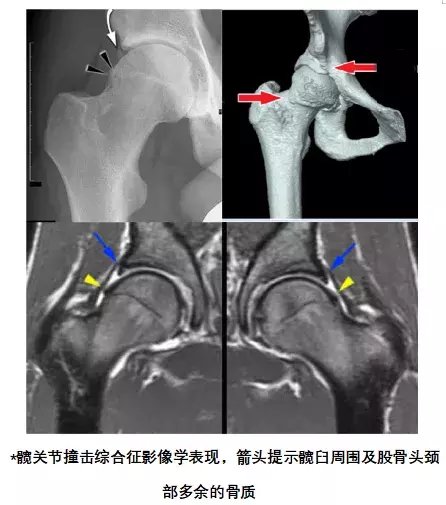

考虑到刘先生髋关节疼痛时间较长,已经保守治疗数月,效果不好,手术指征明显,经科室病例讨论,征得患者及其家属知情同意后,一致决定为刘先生实施髋关节镜微创手术治疗。在科主任郭舒亚的指导下,由丁远景副主任医师主刀为刘先生实施了髋关节镜下股骨头颈成形术、髋臼盂唇修复术,通过2个钥匙孔大小的手术切口,在髋关节镜的监视下,为患者磨除了股骨头颈部多余的骨质,解除了关节内撞击问题,并在关节镜下修复了损伤的盂唇。手术顺利,耗时1小时。术后第一天刘先生即可扶拐下地行走,往日的疼痛不适感消失,带来的是满脸的喜悦和笑容,术后第三天即好转出院。刘先生对手术效果赞不绝口。